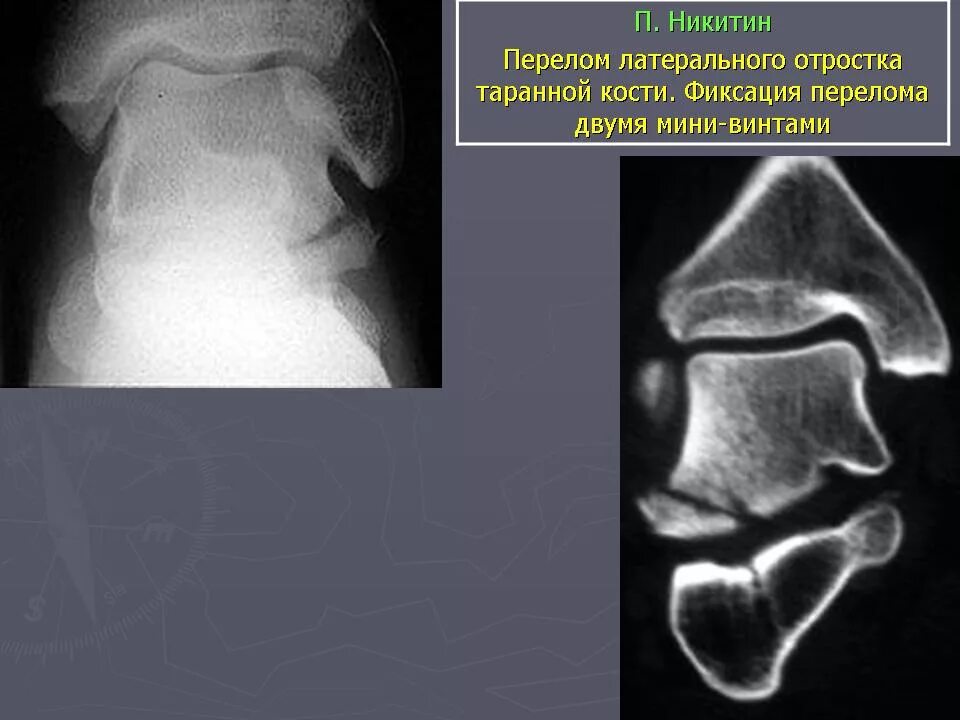

Перелом заднего